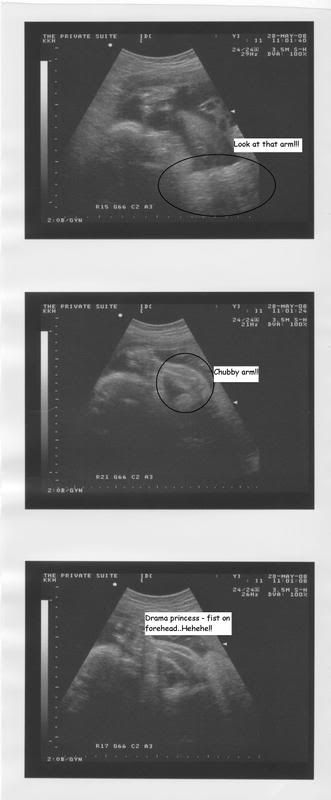

He guffawed, laughed and snorted when I told him what my gynae said about his precious Princess.. :PLet me describe my checkup in greater detail.. :)I was @ ADC for a growth scan, waited so long for my turn..The woman(she was so not helpful and made my Mummy cross..) who scanned me, kept mute all the way..My Mummy prompted her with questions like, 'what is that?', 'Is that the arm?' 'Can you tell the gender?'..That woman only answered when she felt like to and she did say that baby's legs are crossed (again!!!) and based on several more views, its a girl..I asked about baby's weight..I was told baby has reached 2 kg..My mouth gapped..During the last scan 2 weeks ago, my baby was just 1kg..Now 2 kg?!!So we left the ADC, showed my Daddy his granddaughter's scan pic..To that, my Daddy replied, 'Tak de color nyer picture ke?!'Hahahaaaa!!We proceeded to see my gynae with the report..Being kpo, I tried to understand whatever's on the report but failed miserable..I did see that baby's growth was above the 50% percentile in one of the charts..I met my gynae, handed over the report..Gynae took a look at the report..Gynae looked at me, smiling..Gynae: You are having a chubby baby!! (she said it while laughing!)Me: *speechless with mouth wide open*Gynae: A very verrry chubby baby!! (laughing harder after seeing my stunned reaction)My Mummy: How can you tell?Gynae: I look at the chart. Baby's head circumference, bone mass all normal..Her abdomen..Above 50%!!All of us laughed!!I was scanned again and I heard my gynae asking my parents if anyone in the family has diabetes..Apparently if there is, that may be the reason why I am having a chubby baby! But, noone in my family has diabetes..Looks like I am eating too well..Hahaha!!!So I was scanned and my Mummy was there..'Look at that chubby arm!!''Oh, Baby's putting her fist on her forehead''Baby's covering her face''Chubby baby!!'All these were said by my gynae who goodnaturedly demonstrated how my baby was putting her fist on her forehead..Hahaha!!So there you have it..I have a chubby baby..A chubby baby girl..:DAs long as she is healthy, I do not mind how heavy (gulp!) she is..I smsed other family members, close friends and finally revealed Peanut's gender.. :)I smsed DH and told him whatever happened during the checkup,esp about baby's weight..His reply?Short and sweet..'Oh my God! A**** Junior!'*faints*I had a lovely surprise later that evening when DH told me he is booking out..I know he wants to see his Princess!! :DSo back at home, there was no running away from him..DH caught me and grabbed my tummy and talked to his Princess..He insisted to see the pics and guffawed while rubbing my tummy..He laughed even harder when I told him gynae's comments again..Such an excited Abah, he is..The whole night yesterday, he held onto me and talked and talked to his Princess, teasing me along the way..His cheeky Princess obviously loved the attention and kicked furiously when she heard her Abah's voice and felt his touch.. :)Wanna see Peanut?Wait, we cannot call her Peanut anymore!!Why?Based on this,Our baby should weigh 1.3 kg..But our baby now weighs 2 kg!!!So let's call her Princess Pumpkin now..Heheheeeeeee!!I am so gonna romos her cheeks, arms, thighs..I am sure others will as well.. ;)Presenting Princess Pumpkin! I love her to bits!! Heheheeeee!! DH saw the first pic of her chubby arm and exclaimed, 'Michelllliiiiinnnnnnn!!'Hahahaaaaaaaa!!!Oh Princess Pumpkin, all of us love you so much!!PS: DH, I still think PP(Princess Pumpkin) will have your sepet eyes..We obviously know where she gets her chubbiness from! Hahahaaaaa!!